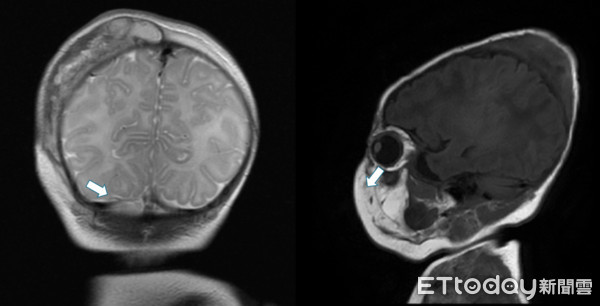

▲男嬰頭皮血腫疑遭按摩按出嚴重感染。(圖/中國附醫提供)

林志鴻說,儘管家長在發現寶寶不對勁時馬上送醫求診,也透過外科手術清除膿瘍,並接受1至2個月的抗傷素治療,但因病嬰年紀小、抵抗力不好,加上病灶位於頭部,3人皆併發腦膜炎或骨髓炎,最嚴重的男嬰甚至有多處腦內膿瘍,留下水腦、慢性癲癇等後遺症。

陳映廷表示,新生兒頭部血腫大多數都侷限在頭皮骨頭外層,不會影響到腦部細胞,但若忽略早期症狀、延誤就醫,局部頭血腫感染有可能進展成腦膜炎、骨髓炎,此時除了治療時程拉長且複雜之外,還有可能造成長期神經發育、發展的影響。